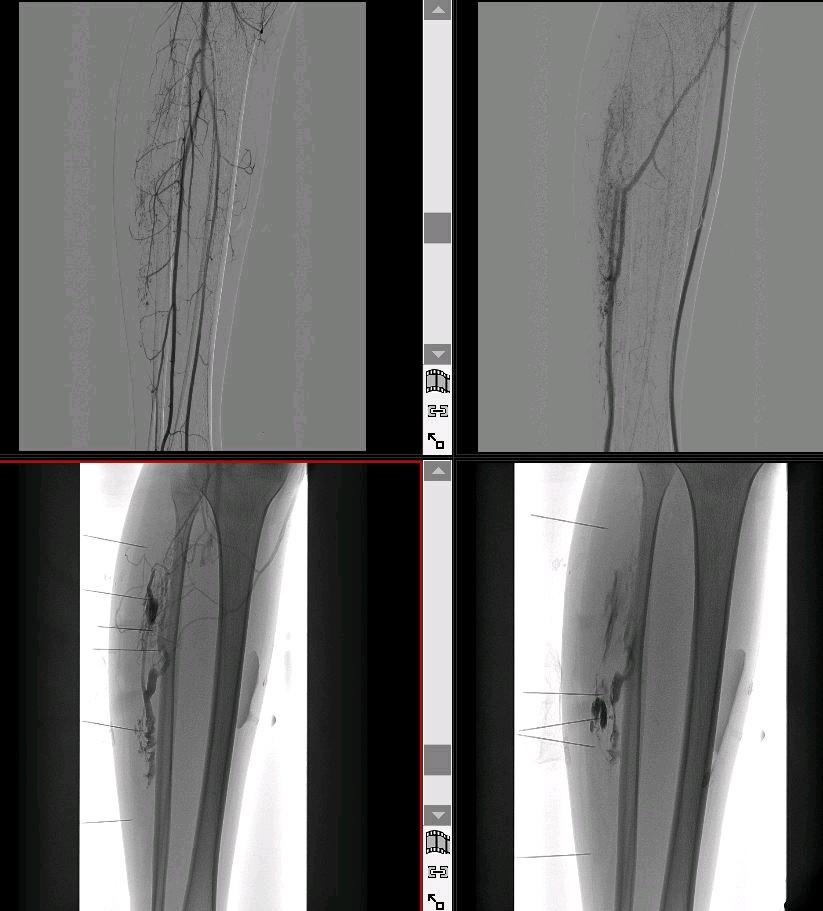

血管造影:可见异常静脉丛,但无动静脉瘘表现。

硬化剂注射:聚多卡醇等药物对部分病例有效,但复发率较高。

无水乙醇栓塞:适用于血管成分丰富的病例,需警惕组织坏死风险。